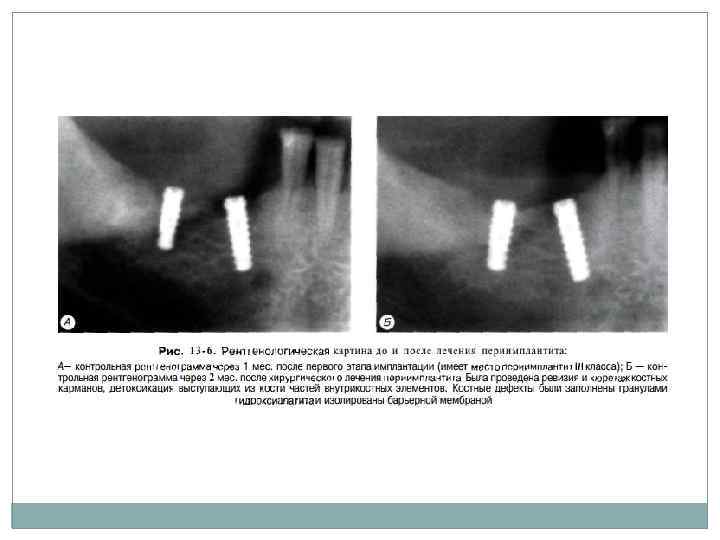

В зависимости от глуби ны и распространения резорбции окружающей имплантат костной ткани S. A. Jovanovic (1990) и Н. Spiekermann (1991) выделяют 4 класса пе риимплантита (рис. 13 3).

При II классе периимплантита. спустя 10 14 дней после купирования воспалительных яв ений, можно произвести хирургическое вмеша тельство. Оно заключается в ревизии костного кармана, обработке и детоксикации поверхности имплантата, заполнении костного кармана остеокондуктивным (лучше в сочетании с остеоиндуктивным) материалом, изоляции имплантата и заполненного остеопластическим материалом дефекта от окружающих тканей при помо щи барьерной мембраны и закрытии операци онной раны. При III классе периимплантита можно про вести такой же курс комплексного лечения, как и при II классе с последующей пластикой кост ного дефекта при помощи методик направлен ной регенерации тканей. Такая схема позволяет добиться восстановления объема кости, окружающей внутрикостный элемент имплантата (рис. 13 6).